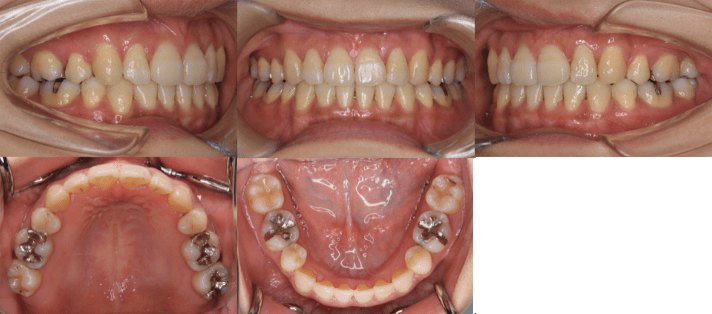

治療後

• 初診時年齢:25歳7ヶ月

• 主訴:前歯のガタガタ

• 診断:交叉咬合を伴う叢生症例

• 抜歯箇所:上顎左右4、下顎左右5

• 治療内容:小臼歯4本を抜歯した後、マウスピース型カスタムメイド矯正歯科装置(製品名インビザライン 完成物薬機法対象外)を使用して主訴である叢生の改善を行いました。

• 治療期間:2年

• リスク:矯正治療による歯の移動に伴う痛み、歯根吸収、虫歯

• 費用:88万円